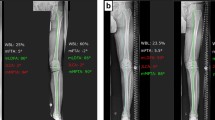

A computed tomography (CT) scan of the patient’s right knee was performed with a slice thickness of 1 mm. Digital Imaging and Communications in Medicine (DICOM) data were extracted by proprietary software (Bodycad Imager, Bodycad, Quebec, Canada), and a 3D model of the femur, tibia, and fibula was created. The pre-operative planning was performed using the Bodycad Osteotomy software package (Bodycad, Quebec, Canada). True anteroposterior (AP) and lateral views were created by overlapping the bone model on the patient’s long-standing AP radiograph (Fig. 1). Different landmarks were positioned over the 3D bone model by the software; pre-operative measurements and angles such as MPTA (medial proximal tibial angle), LDFA (lateral distal femoral angle), HKA (hip-knee-ankle), and tibial slope were calculated (Fig. 2). The patient had a normal JLCA (joint line convergence angle) value of 1.07°, a tibiofemoral varus alignment of 5.74°, a MPTA of 84.42°, and medial and lateral tibial slope of 7.40° and 13.47°, respectively.

Following the final checks by the senior author and surgeon, the simulated osteotomy and correction were made using the Bodycad Osteotomy software. The WBL (weight-bearing line) correction to 55% of the tibial plateau width was chosen. An opening of 10.21 mm was calculated by the software to obtain this particular correction. The resulting patient’s lower limb alignment was calculated to be a tibiofemoral valgus alignment of 1.69° and a MPTA of 91.86°, with no change of the tibial slope (Figs. 3, 4). The hinge axis was planned to be at an ideal position of 15 mm from the lateral plateau and 10 mm from the lateral cortex. A biplane cut was proposed due to the tibial tuberosity that was in the way of the osteotomy cutting plane. The cut was positioned just below the ACL screw (Fig. 5). Approval of the pre-operative planning was done prior to manufacturing the patient-specific surgical guide and plate (Figs. 6, 7 and 8).